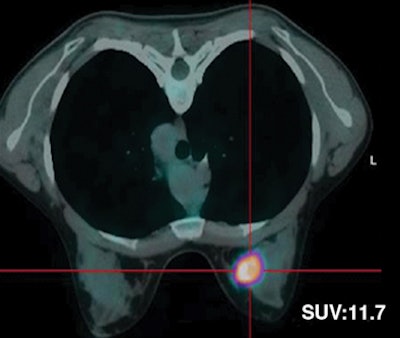

| Thirty-two-year-old woman with ductal infiltrating adenocarcinoma measuring 18 mm in maximum transverse diameter. Axial fused PET/CT images obtained with patient in prone position at time point 1 (above) and time point 2 (below) show corresponding standard uptake values. |